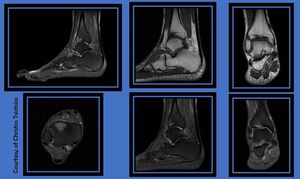

High resolution ankle MR Imaging based on a whole foot Sagittal PD-w FS, very useful for pathology detection, and five localized sequences. Scan time less than 17 minutes.